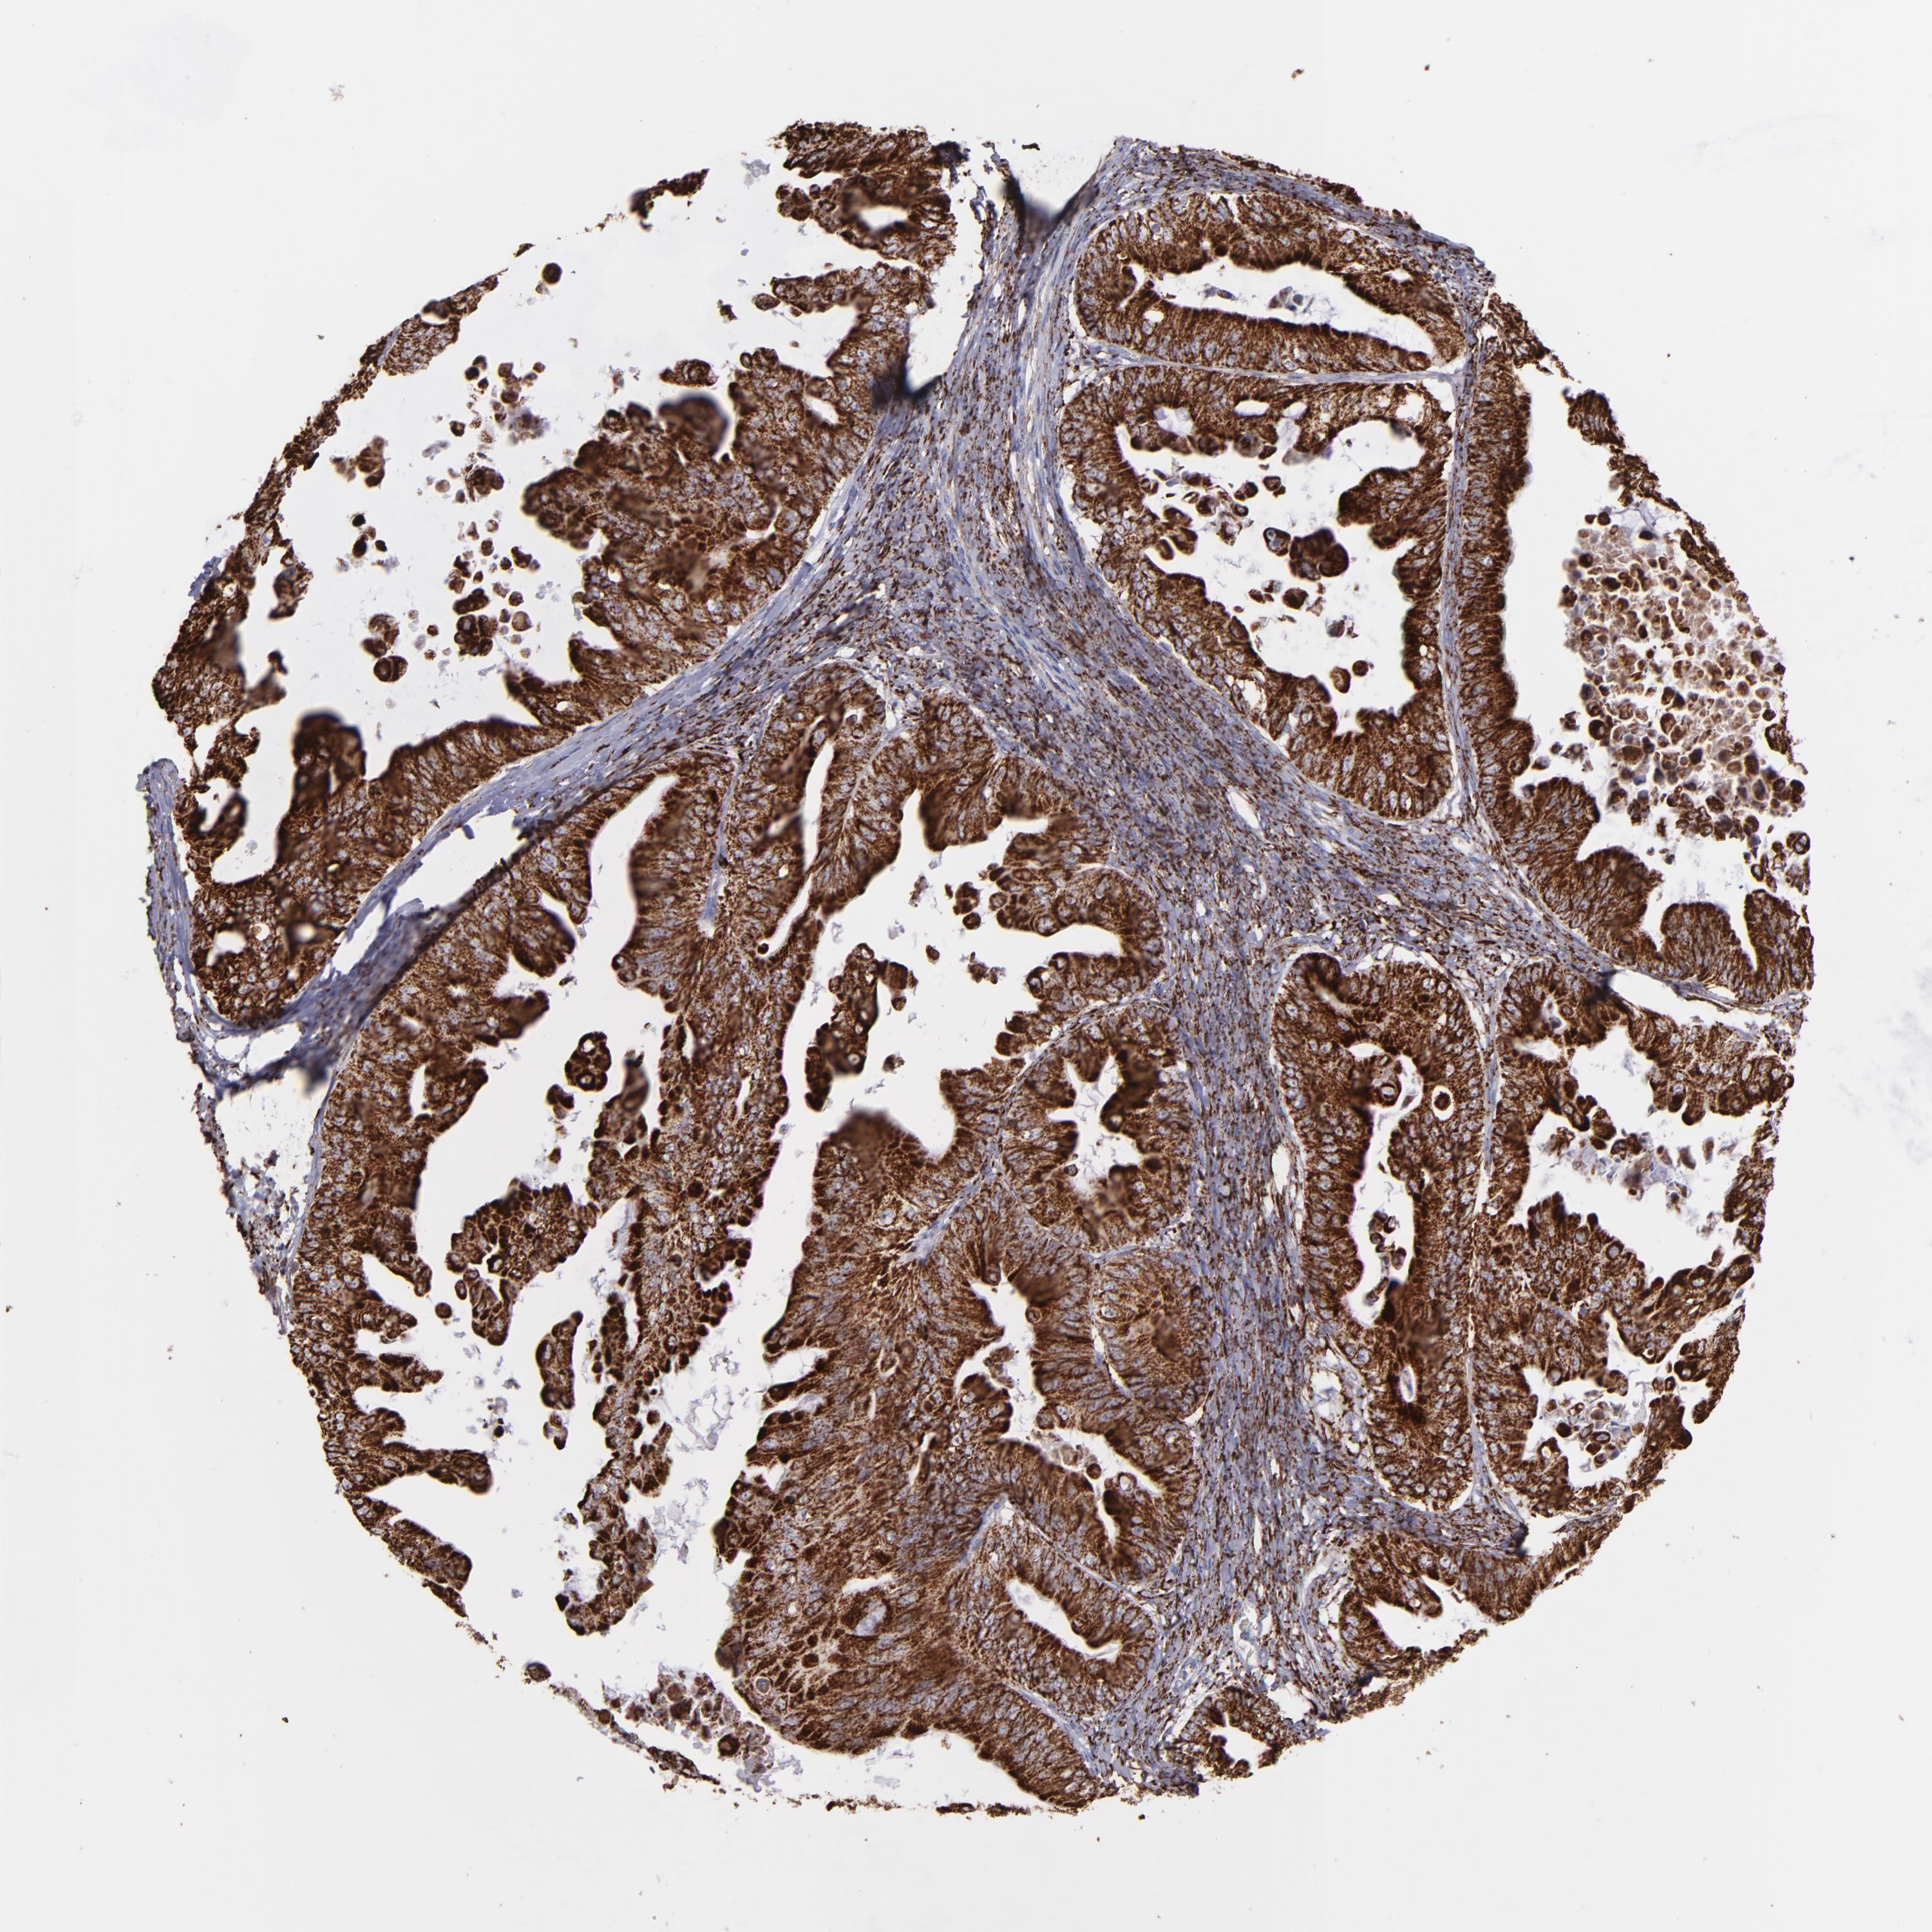

OVARIAN CANCER - Protein expressioni

A mouse-over function shows sample information and annotation data. Click on an image to view it in a full screen mode. Samples can be filtered based on level of antibody staining by selecting one or several of the following categories: high, medium, low and not detected. The assay and annotation is described here.

Note that samples used for immunohistochemistry by the Human Protein Atlas do not correspond to samples in the TCGA dataset.

Antibody stainingi

Antibody staining in the annotated cell types in the current human tissue is reported as not detected, low, medium, or high, based on conventional immunohistochemistry profiling in selected tissues. This score is based on the combination of the staining intensity and fraction of stained cells.

Each image is clickable and will lead to virtual microscopy that enables deeper exploration of all samples and also displays staining intensity scores, fraction scores and subcellular localization as well as patient and tissue information for each sample.

Antibody HPA002328

Antibody CAB037200

Cystadenocarcinoma, serous, NOS